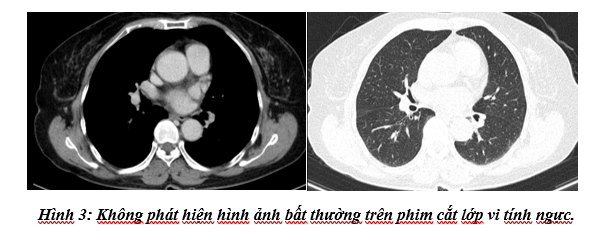

Cắt lớp vi tính ngực: Không phát hiện tổn thương bất thường.